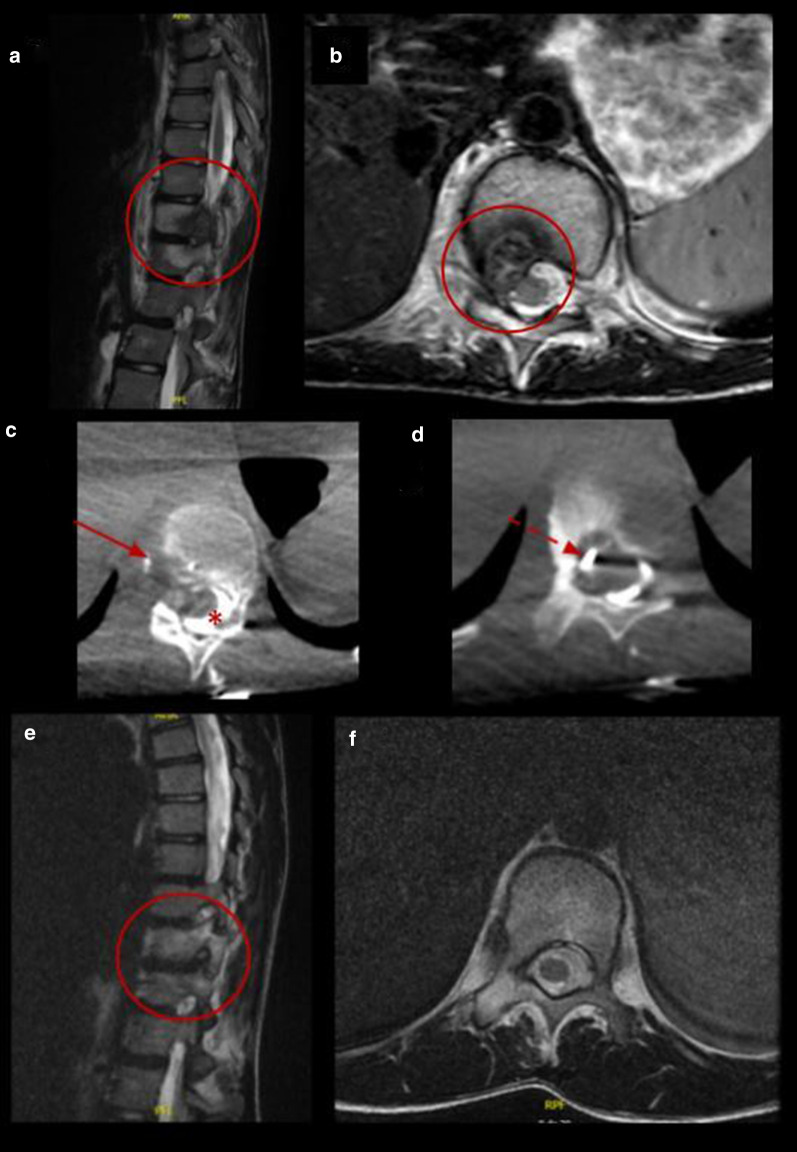

Fig. 3.

Percutaneous cryoablation of vertebral osteoblastoma in a 14-y.o patient. a, b Sagittal and axial T2 MR images show a lobulated lesion located in the posterior aspect of the body of the 11th thoracic vertebra (red circle). c, d Cryoablation of OB (arrows). Cone beam CT axial reconstruction of the cryoprobe and epidural hydrodissection (asterisk). e, f Follow-up MRI 12 months after procedure with complete resolution of the lesion (red circle)